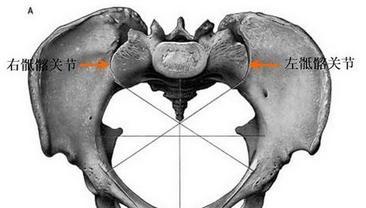

骶髂關(guān)節(jié)位于人體臀部,好發(fā)骶髂關(guān)節(jié)炎,骶髂關(guān)節(jié)炎是一種常見(jiàn)多發(fā)病,多由其它疾病繼發(fā)而來(lái),易診難治,特點(diǎn)為隱匿發(fā)作、持續(xù)鈍痛,嚴(yán)重影響了患者的身心健康。退變性骶髂關(guān)節(jié)炎多見(jiàn)于中老年尤以女性為多,主要表現(xiàn)為骶髂關(guān)節(jié)局部的疼痛及壓痛;強(qiáng)直性骶髂關(guān)節(jié)炎多見(jiàn)于青年人,是強(qiáng)直性脊柱炎的一個(gè)表現(xiàn)。